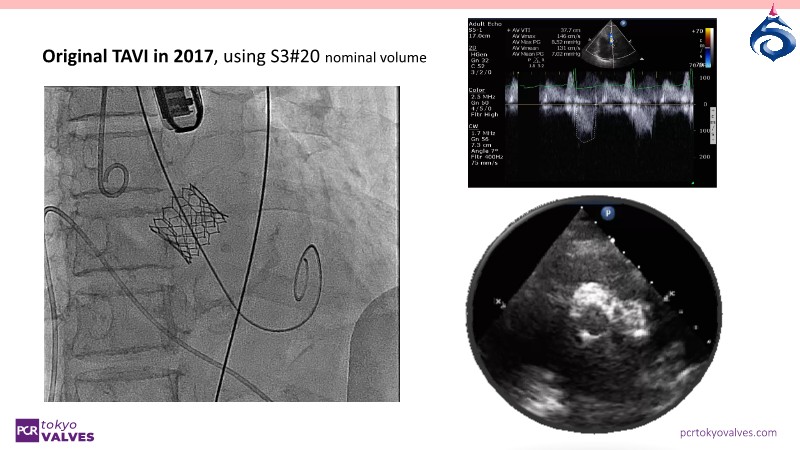

Watch this expert-led session on the latest Evolut TAVI advancements, device selection for small annulus cases, and strategies for complex anatomies. Learn about redo-TAVI feasibility and key 1-year data from the SMART trial.

• To evaluate the feasibility of future redo-TAVI procedures when performing TAVI in patients with long life expectancy